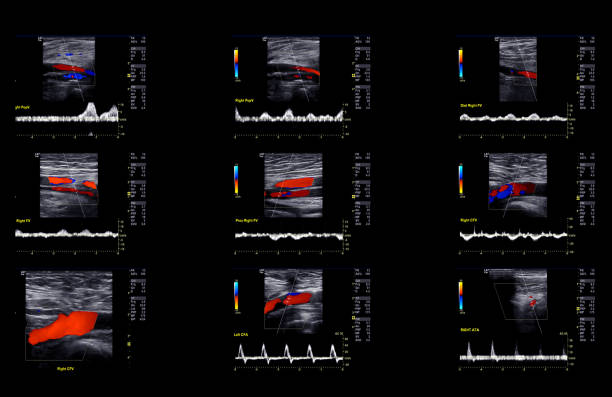

검사 결과를 해석할 때, 의사는 다음 사항을 고려합니다.

- 경동맥의 크기와 형태: 경동맥이 충분히 넓고 매끄럽게 유지되는지 확인합니다.

- 혈류 속도: 혈액이 경동맥을 흐르는 속도를 측정하여 혈액순환에 이상이 없는지 확인합니다.

- 혈액 응고물질의 존재: 콜레스테롤과 혈액 응고물질이 경동맥 벽에 쌓여 있는지 확인합니다.